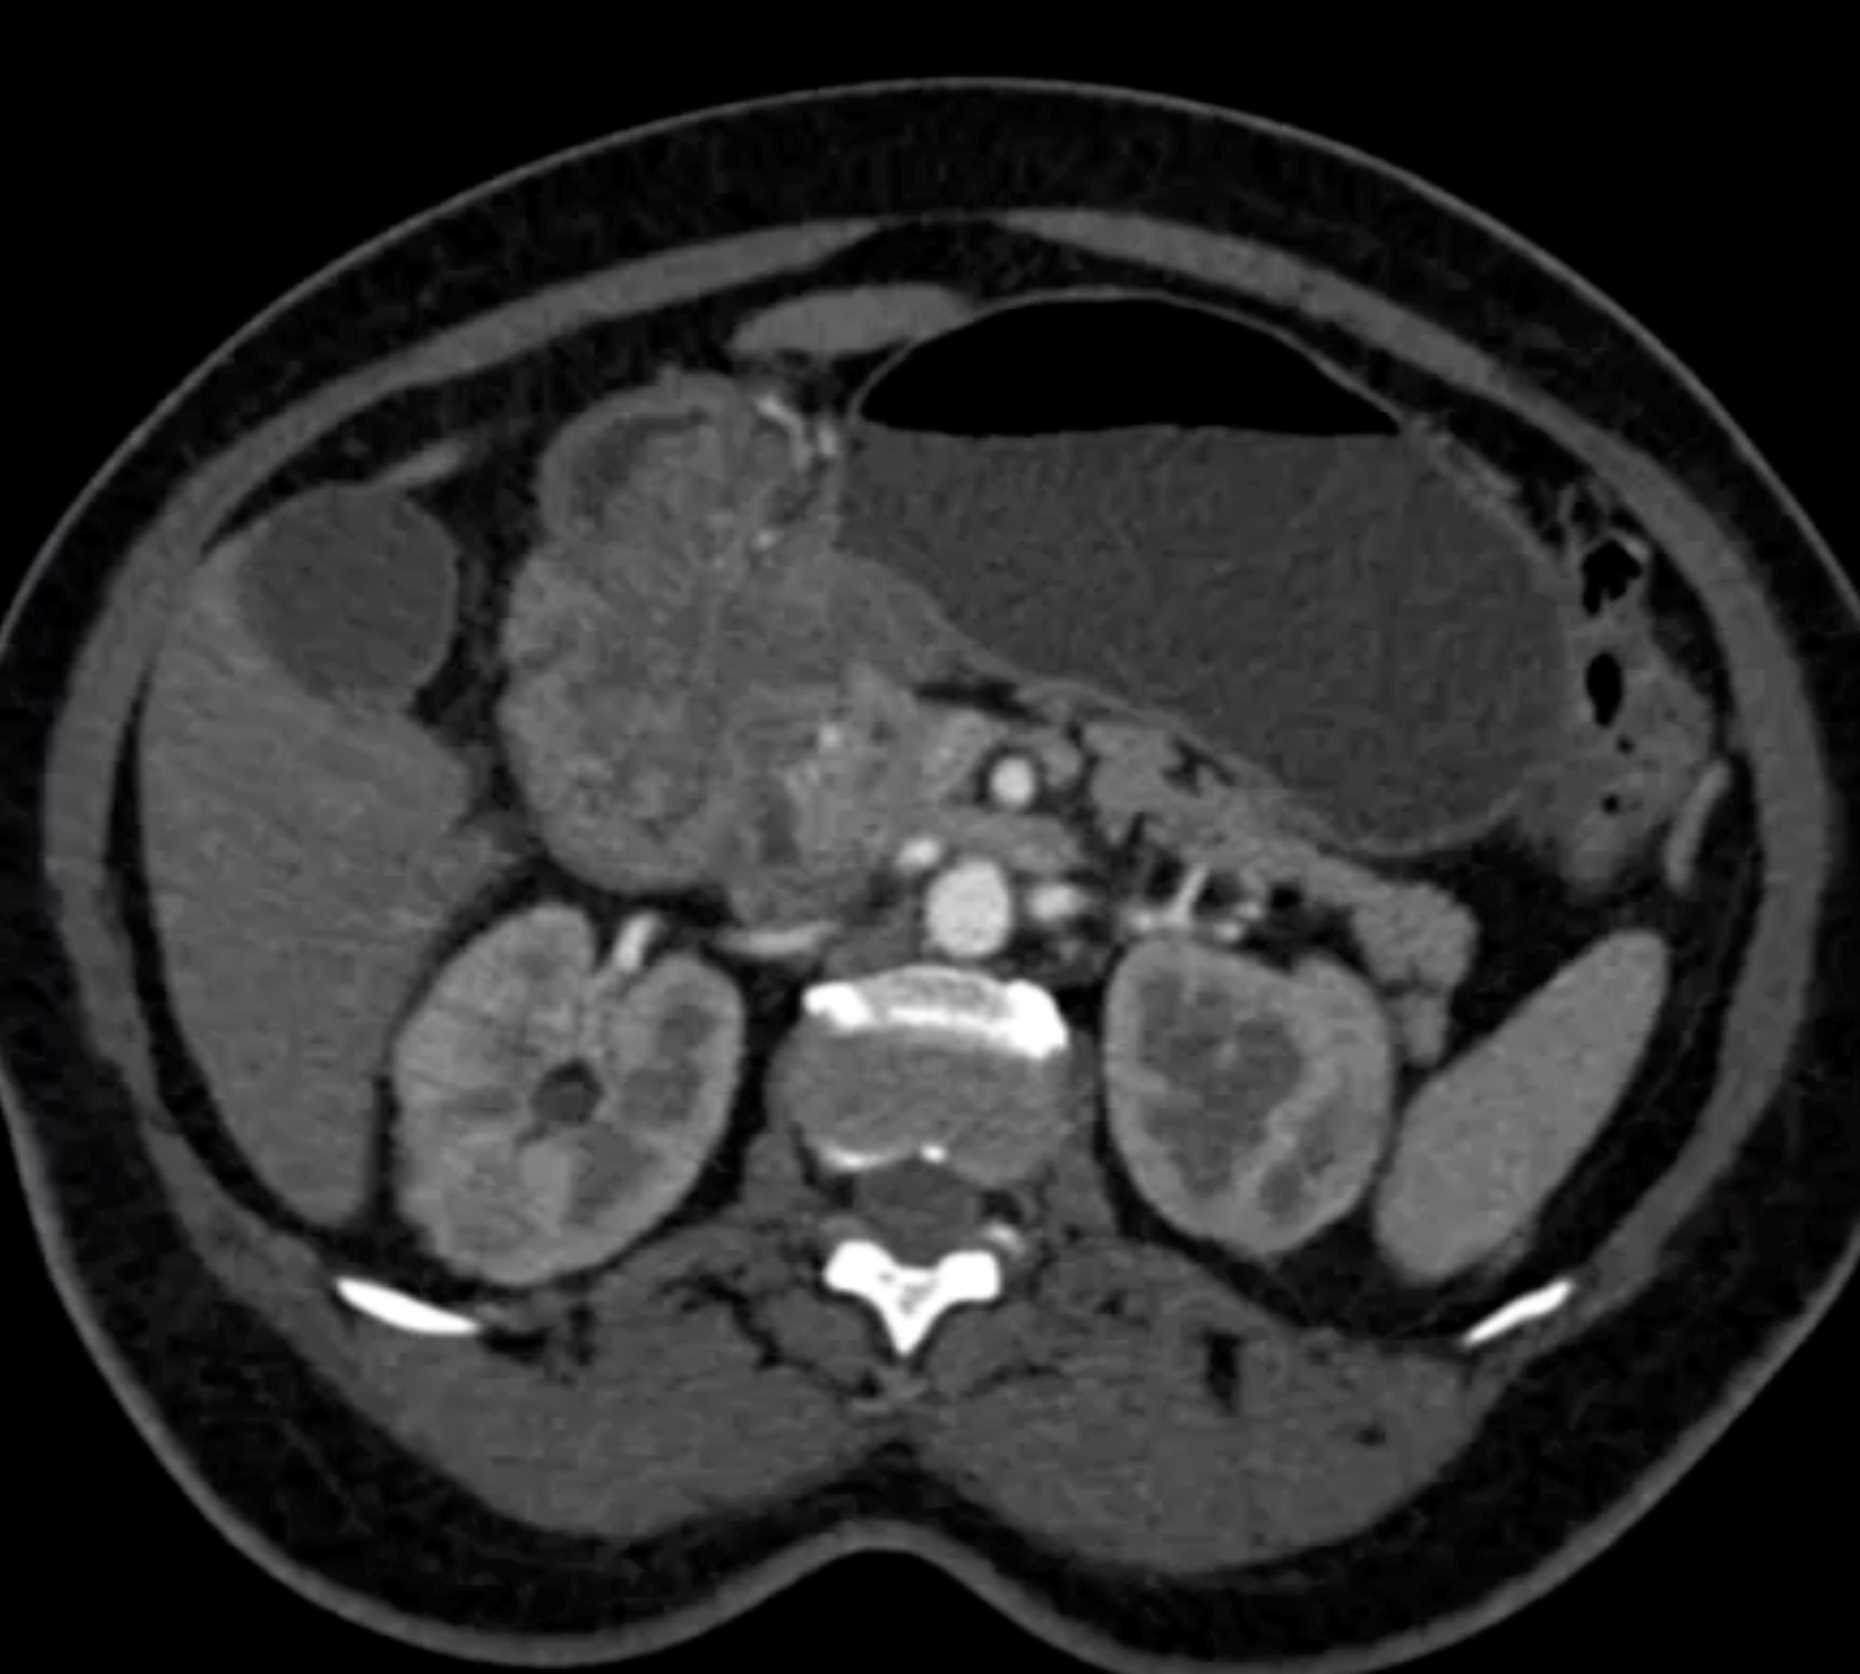

Lagre Gastric GIST Tumor